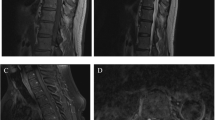

A 67-year-old man presented with a 4-month history of back pain and sciatica and a 4-week history of progressive lower extremity paresthesia, difficulty walking, and loss of bladder and bowel sphincter control. Neurological examination revealed bilateral hypoesthesia below the T12 dermatome with spastic paraparesis. Magnetic resonance imaging (MRI) of the cauda equina revealed a heterogeneous enhancing intradural extramedullary mass obliterating the spinal canal and expanding the spinal cord. T12 laminectomy and total tumor removal were performed without additional neurological deficit. Pathological examination confirmed the diagnosis of a CA.